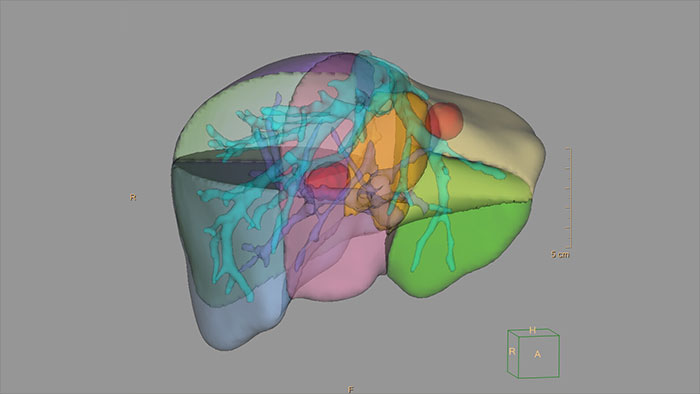

3D Modeling

Streamlined modeling workflow

Allows to view volumetric images of anatomical structures, perform segmentation, edit and combine segmented elements (tissues) into a 3D model.

Benefits

- Studies of CT & MR can be used for creating a single 3D model of the same patient. The application provides tools that allow the user to align between the volumes of interest in the images.

- 3D Modeling batches files can be easily exported in standard formats such as STL, with the option to also provide a 3D PDF as an additional means for results sharing with 3D printing or other services* .

- The user may determine the information related to the exported elements of the 3D model such as smoothness and output mesh size.

- Contours can also be exported as RT Structures.

*3D models are not intended for diagnostic use.